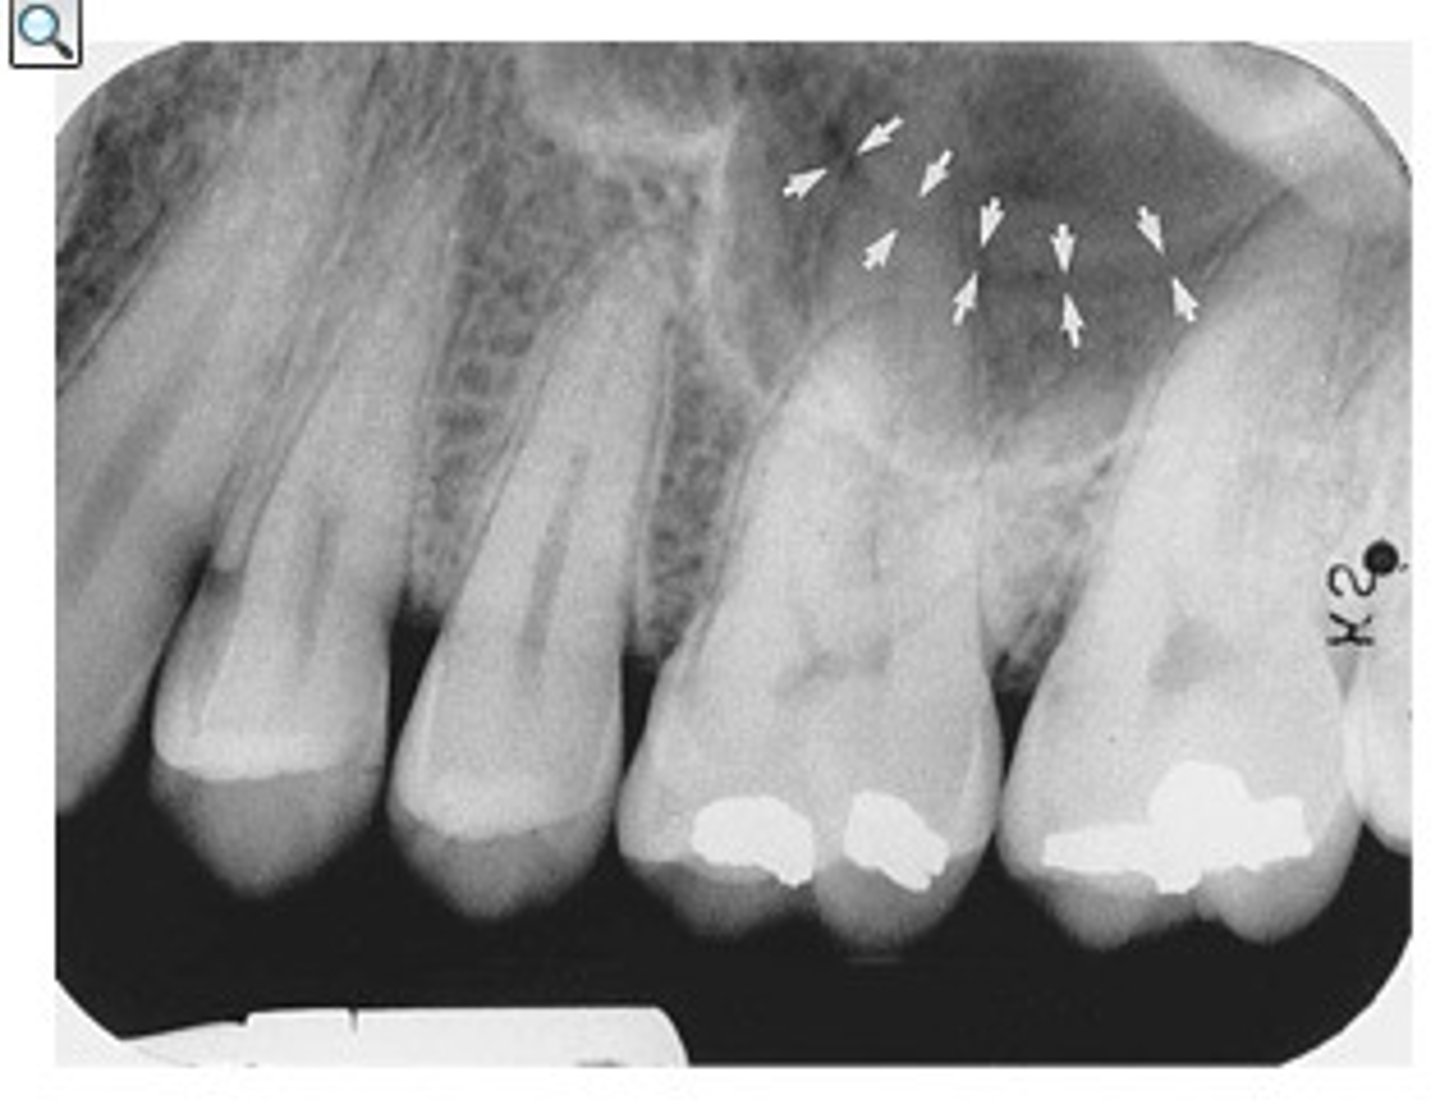

Nutrient canals within the maxillary sinus

What is the radiolucent structure seen here?